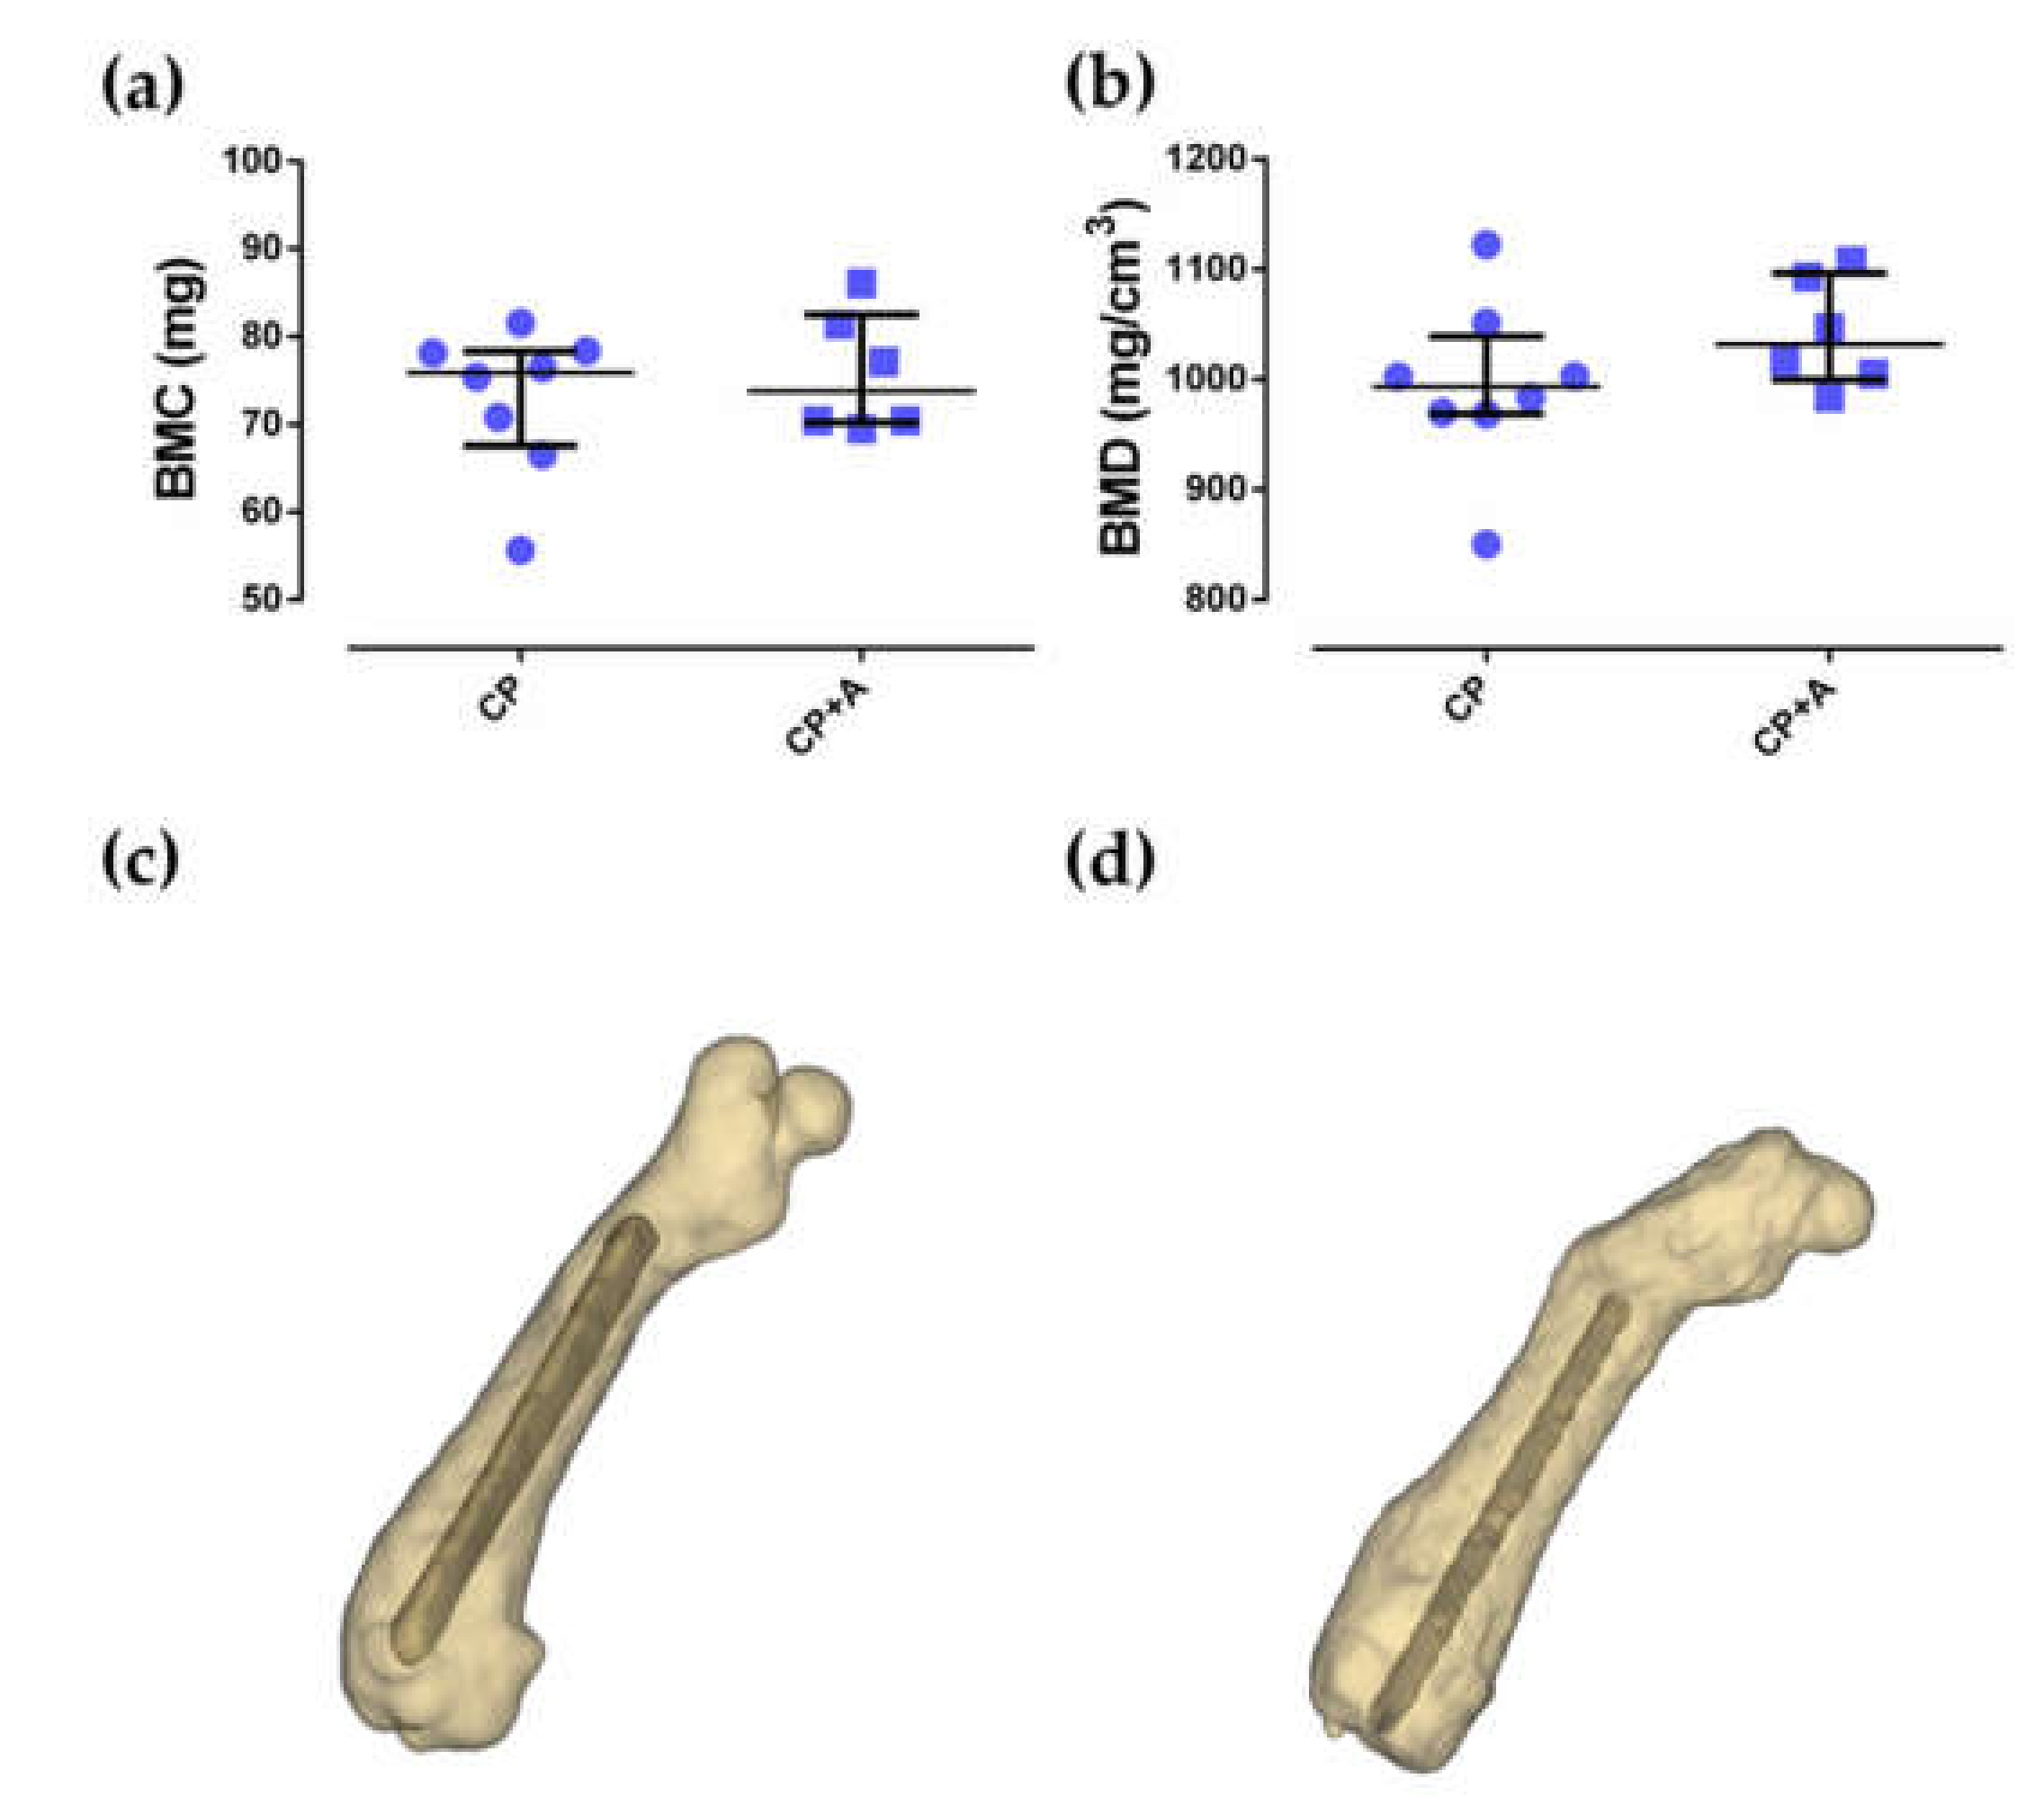

2.3. Microcomputed Tomography and Bone Histology

4.4. Microcomputed Tomography